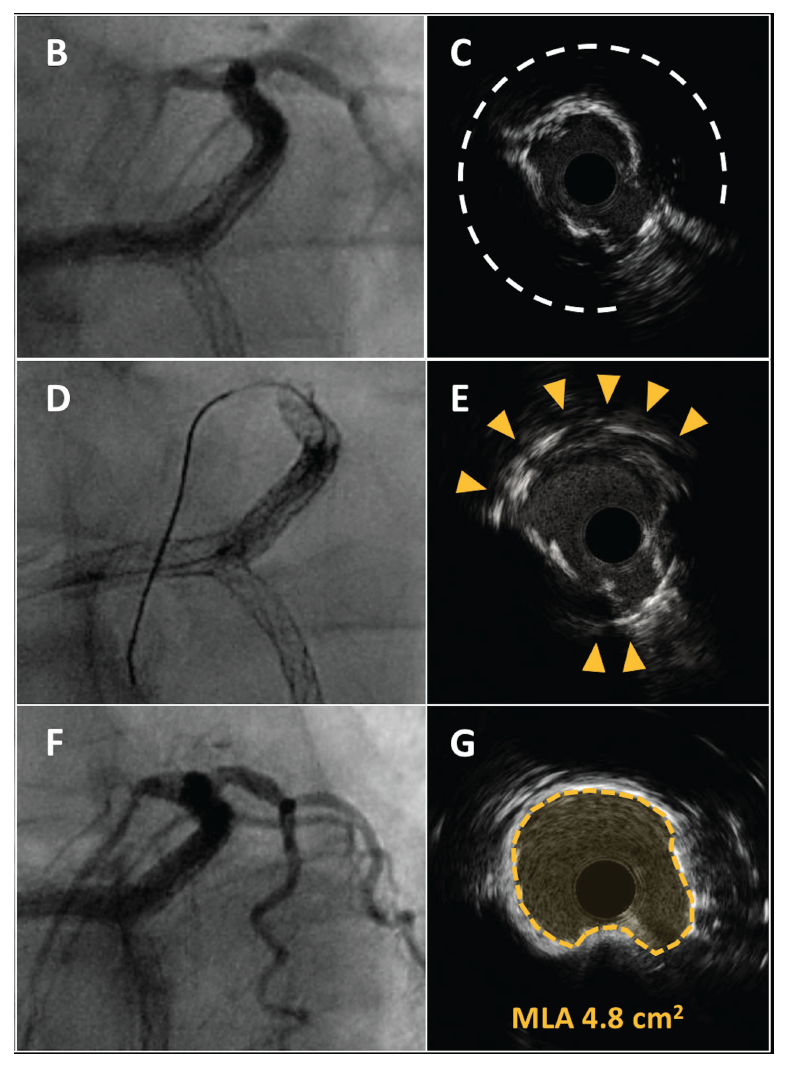

A 69-year-old man with prior history of coronary artery bypass graft surgery with saphenous vein graft (SVG) for the left anterior descending (LAD) and jump to the first diagonal (D1) underwent multiple percutaneous coronary interventions with drug-eluting stent (DES) implantation on the graft, due to aggressive in-stent restenosis (ISR), and on mid-distal LAD with multiple stents resulting in in-stent chronic total occlusion with no recanalization options because of inability to visualize the distal vessel. The patient was admitted to our institution due to worsening effort angina. He was already on optimal medical therapy. He underwent coronary angiography via radial approach, which showed subocclusive ISR in the SVG (Figures 1A and 1B). Patency of the other grafts was documented and no other revascularization target was identified. Intravascular ultrasound (IVUS) showed 270°, severely calcific ISR with at least 2 layers of previously implanted stent struts (Figure 1C). Considering the severe lesion calcification and perforation after non-compliant balloon dilation during a prior procedure, we decided to perform intracoronary lithotripsy. A 3.5 mm intravascular lithotripsy balloon (Shockwave Medical) was used and 8 balloon inflations were performed with IVUS documentation of cracked calcium (Figures 1D and 1E). After 3.5 mm non-compliant balloon dilation, a new-generation 3.5 x 20 mm DES was implanted and postdilated with good angiographic result (Figure 1F). IVUS showed acute gain in minimal luminal area (Figure 1G).